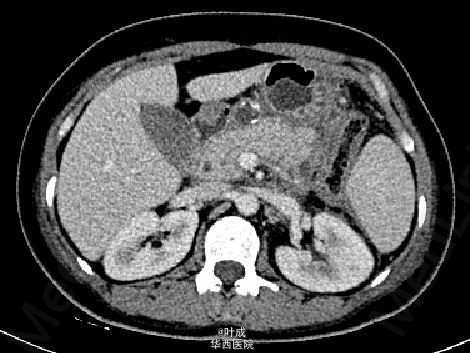

患者女,40岁,因“反复腹痛5+年,复发加重1+天”入院。急诊查血清AMS 2349 IU/L、 LIP 6647 IU/L,腹部CT平扫示胰腺肿胀,胰周渗出,腹膜炎征象。下为起病四天后复查增强CT影像。